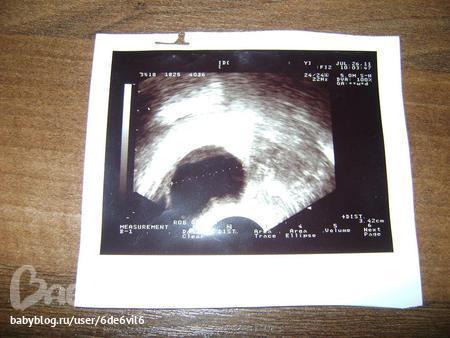

мне просто давали все фоты когда я на фолликулометрию ходила)))хотите я выложу фото фолликулярной кисты?чтоб наглядно было?

это дом.фолликул к.т не лопнул после уколов прегнила(из-за того что дюф начала пить до О)размер где-то 30мм.Если вы такого на экране не монитора не видели,значит он лопнул.